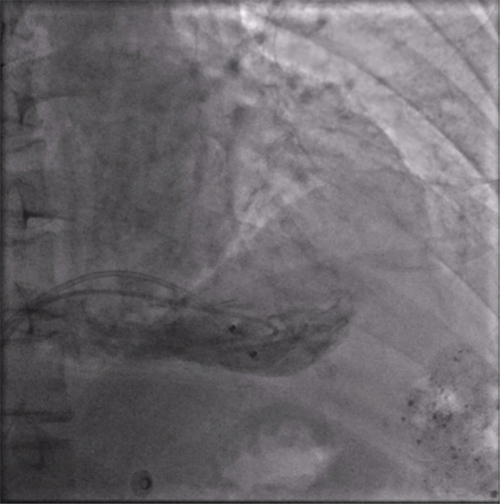

经过周密的术前准备,彭晖、孙志军两位主任带领邸北冰主治医师、柳晓娜主治医师和梁立丰医师在内的起搏电生理团队,于心脏介入手术室为患者实施手术。手术团队股静脉穿刺成功后,首先对下腔静脉进行造影并将外鞘放置送入下腔静脉,随后将新型主动固定螺旋无导线起搏器顺利跨瓣送入右心室目标位置,旋入前测试无导线起搏器各项电学参数良好,确认位置合适后旋入固定起搏器,在植入过程中动态测试起搏器各项参数以辅助判断固定程度,达到标准后进入对接栓模式,再次测试起搏器固定位置稳定、各项参数良好后释放起搏器,最后撤出鞘管,顺利完成手术。整个手术流程高效有序,医疗团队成员紧密配合,默契无间,仅耗时40分钟共同完成了这一具有挑战性的任务。

右室猪尾导管造影